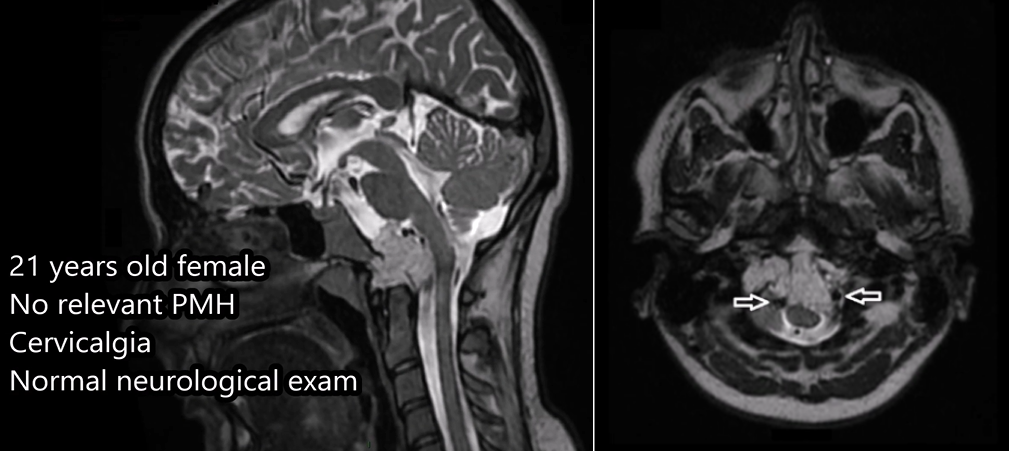

21岁女性,因颈部疼痛发现枕骨大孔和颅颈交界区的脊索瘤,病变拓展至硬膜内,累及双侧椎动脉。该名脊索瘤患者还伴有明显的骨质破坏和硬膜内延伸。

03、21岁女性脊索瘤

这位年轻女性因颈部疼痛就诊,MRI发现颅颈交界区脊索瘤,伴骨质破坏和硬膜内延伸,累及双侧椎动脉。